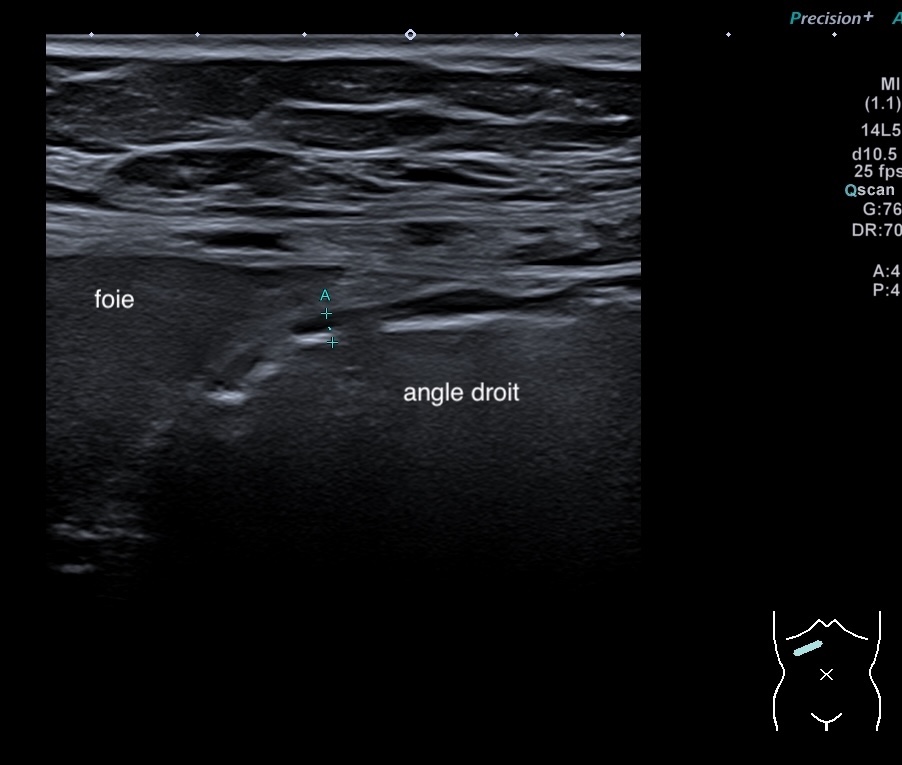

Echographie: pancolite jusqu’à l’angle droit, Paroi 7 mm perte de la stratification, doppler positif.

Epaississement entre 4.5 et 7 mm selon les segment, la structure en couche disparait totalement par endroit, à d’autre elle est partiellement conservée. Activité doppler intense de la paroi

Le Score de Milan (MUC) est à (1,4 x7+2) = 11,8